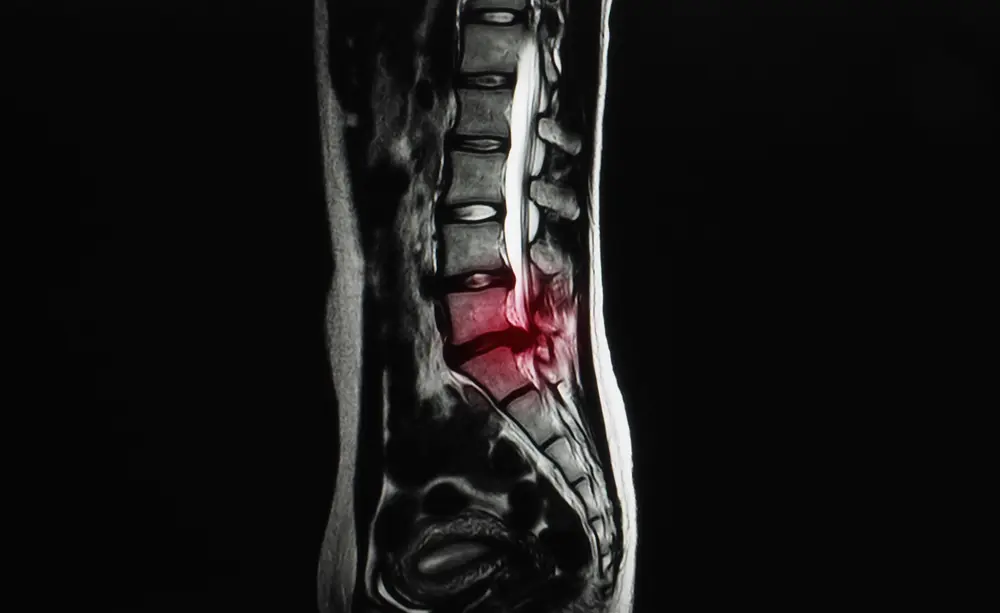

Sagittal MRI of lumbar spine showing herniated intervertebral disc at L5/S1, illustrating cause of back pain and sciatica.